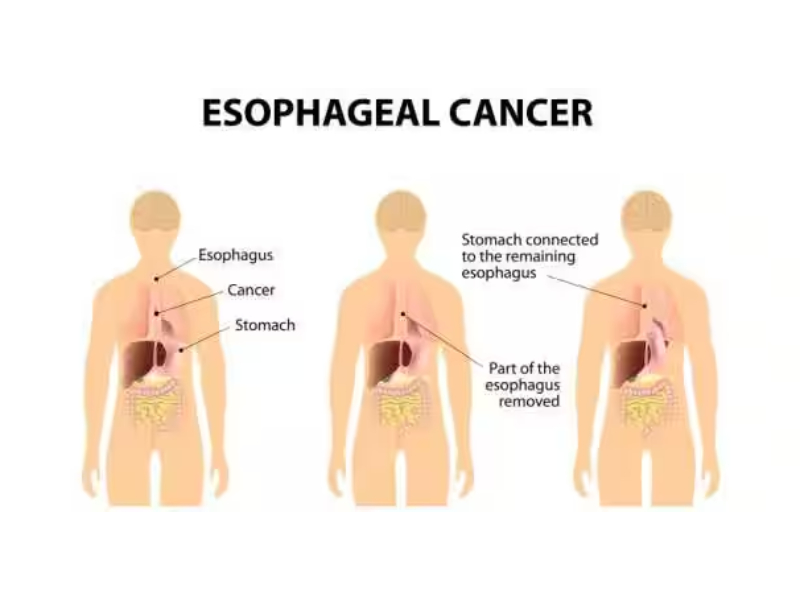

Tumors & Cancers

Discover symptoms & explore medicines and treatment options. Also read expert health articles about symptoms, the latest research, medicines and alternative treatments for every disease and medical condition.